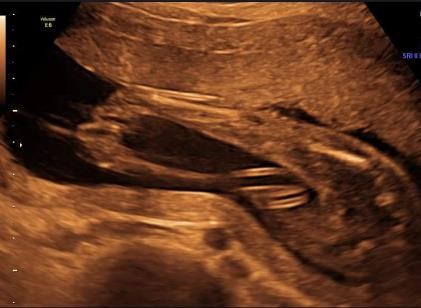

W listopadzie ma przyjść na świat nasza ukochana Julcia.W 21 tygodniu ciąży usłyszeliśmy od lekarza, że nasza córeczka urodzi się z poważną wadą stópek (SKS), tą wiadomość była straszna i nie do przyjęcia. Rozpacz jaka nas ogarnęła nie ma końca.